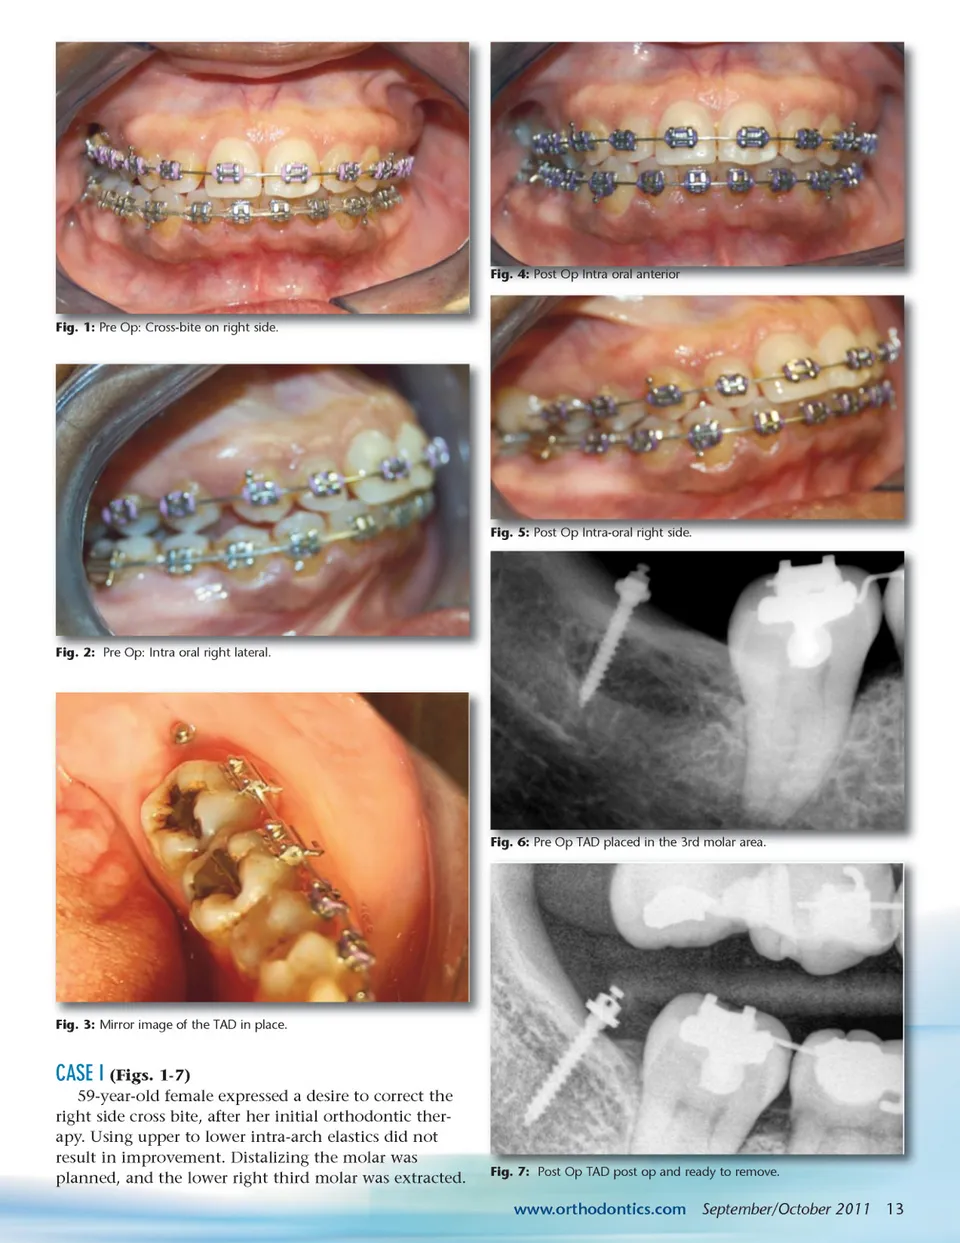

IMPROVING ANCHORAGE: TADs Use in Orthodontic Treatment Plans Deciding on which anchorage to use during orthodontic treatment plays a very important role in the final outcome. There are many intra-oral and extra-oral systems available, but most of them require patient compliance to prevent undesired tooth movement. Many of these undesired movements can be eliminated by the use of TADs. By Anilesh Katte, DDS, MAGD, Anuja Patel, BDS, MBA, Vikaskumar Patel, BDS, MBA, and Jim R. Prittinen, DDS emporary Anchorage Devices (TADs) are mini screws made of titanium. They are 1-to 2-mm in diameter and 6-to 12-mm in length. They are placed in the bone temporarily to improve orthodontic anchorage. 1 The use of temporary devices for skeletal anchorage was first proposed in 1945. 2 Since this introduction, TADs have gone through various changes in design and size. The U.S. Food and Drug Administration has given TADs its approval. 3 TADs have made it possible to almost totally eliminate the use of extra-oral headgear in many cases. Use of this mini screw technique can be applied, for example, in treatment of super-erupted molars. It also minimizes the need for patient compliance and thus increases the success of the orthodontic treatment. T In order to achieve successful temporary anchorage, proper site selection is critical. Placement of TADs in thick cortical bone gives more strength. 4 Even though TADs can be placed both bucally and palatally, it is necessary to take into account the patient’s growth phase. In growing patients, placement of TADs near the maxillary palatal suture site is contraindicated. 5, 6 Patients who are heavy smokers are poor candidates for the appli-cation of TADs. 7 Placing TADs in attached gingiva can eliminate soft tissue problems that sometimes occur when TADs are placed in mucobuccal gingiva. INDICATIONS í í í í Molar uprighting Molar intrusion Edentulous space closure Impacted canine: Either mesial or distal movement is possible í Forced eruption of unerupted teeth í Anterior open and deep bite correction. SITE SELECTION & PROCEDURE Temporary anchorage placement can be accom-plished as a minimally invasive procedure with just topical anesthesia. Local infiltration anesthesia and other methods of anesthesia can also be used if the clinician deems it necessary. TADs can be directly inserted through the gingiva. Various types of TADs are available, for example, self-drilling or self-tapping. Either one can be placed with the hand driver instru-ment provided with the kit. TADS are intended to be removed after completion of successful treatment. Removals of TAD are also done with use of a manual screwdriver tool provided with the kit. In order to eliminate any risk of swallow-ing the TAD, tying of the head of the screw with floss is recommended. 12 September/October 2011 JAOS CONTRAINDICATIONS í í í í í í Patient undergoing radiation therapy Presence of oral infection Heavy smokers History of metabolic disorders Diabetes, osteoporosis, osteomyelitis Poor periodontal support or presence of periodontitis í Poor bone support for placing mini implant